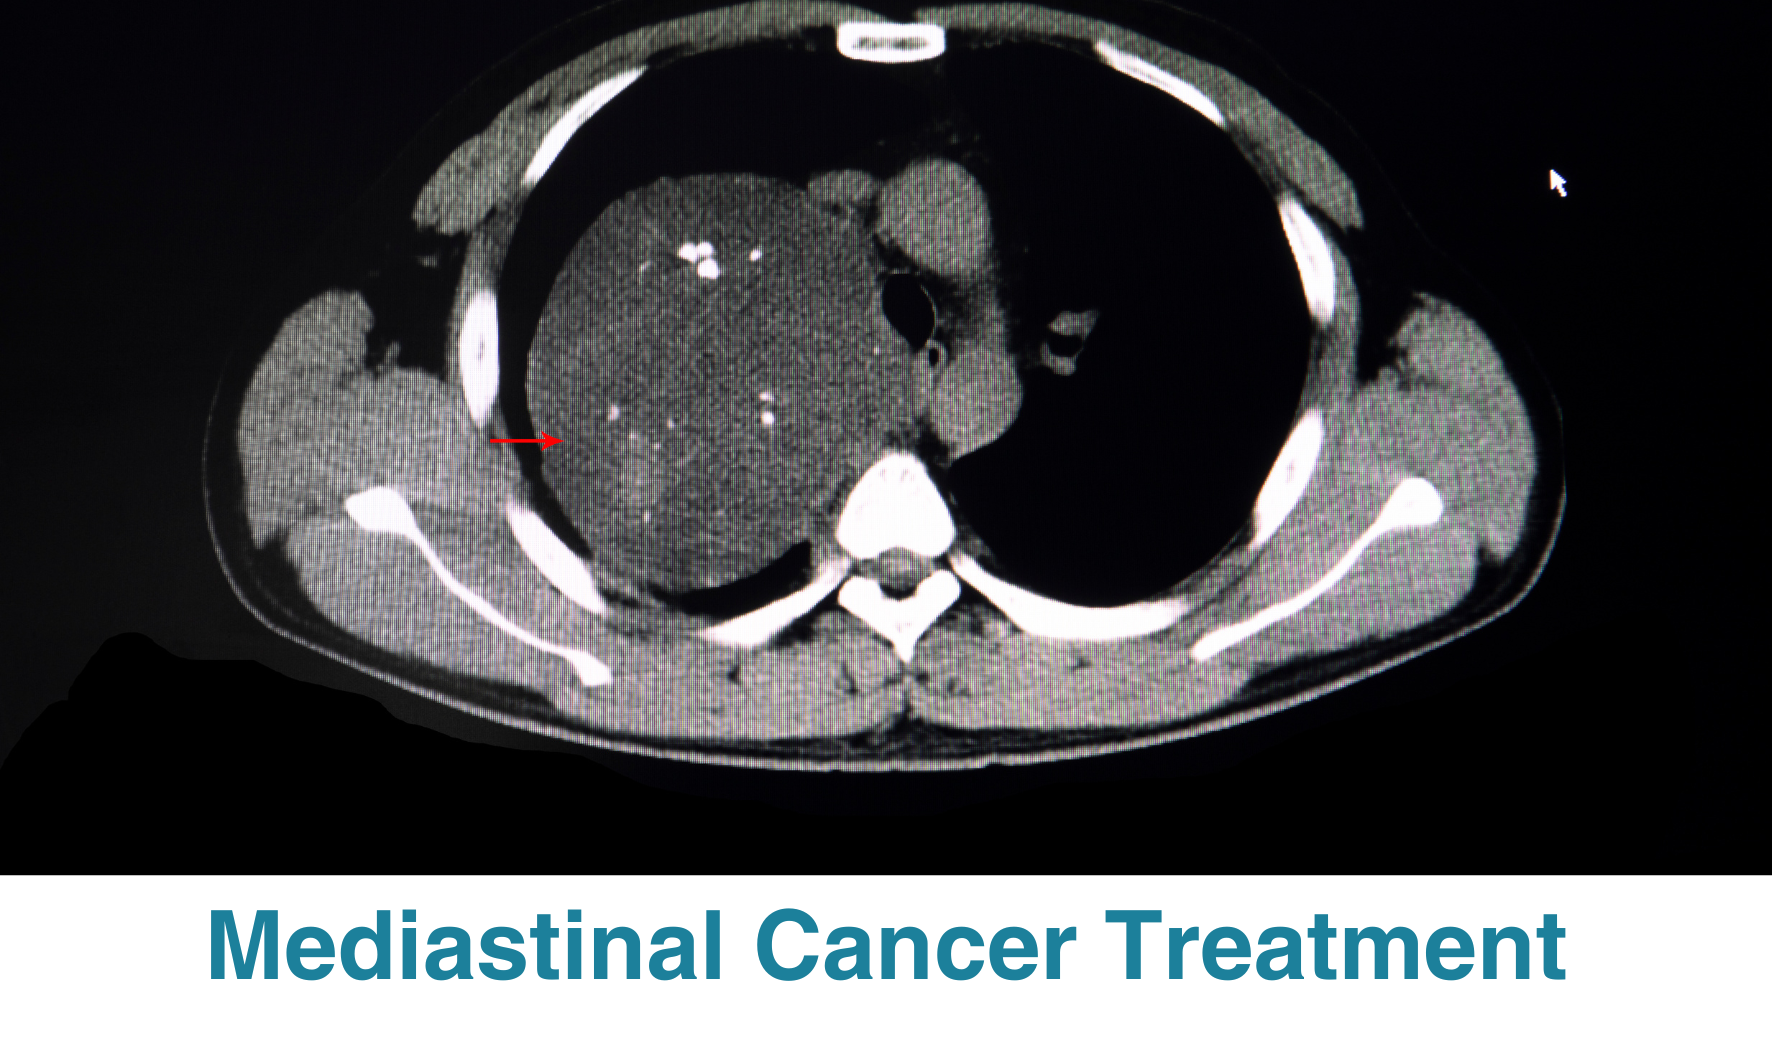

Mediastinal Cancer Treatment